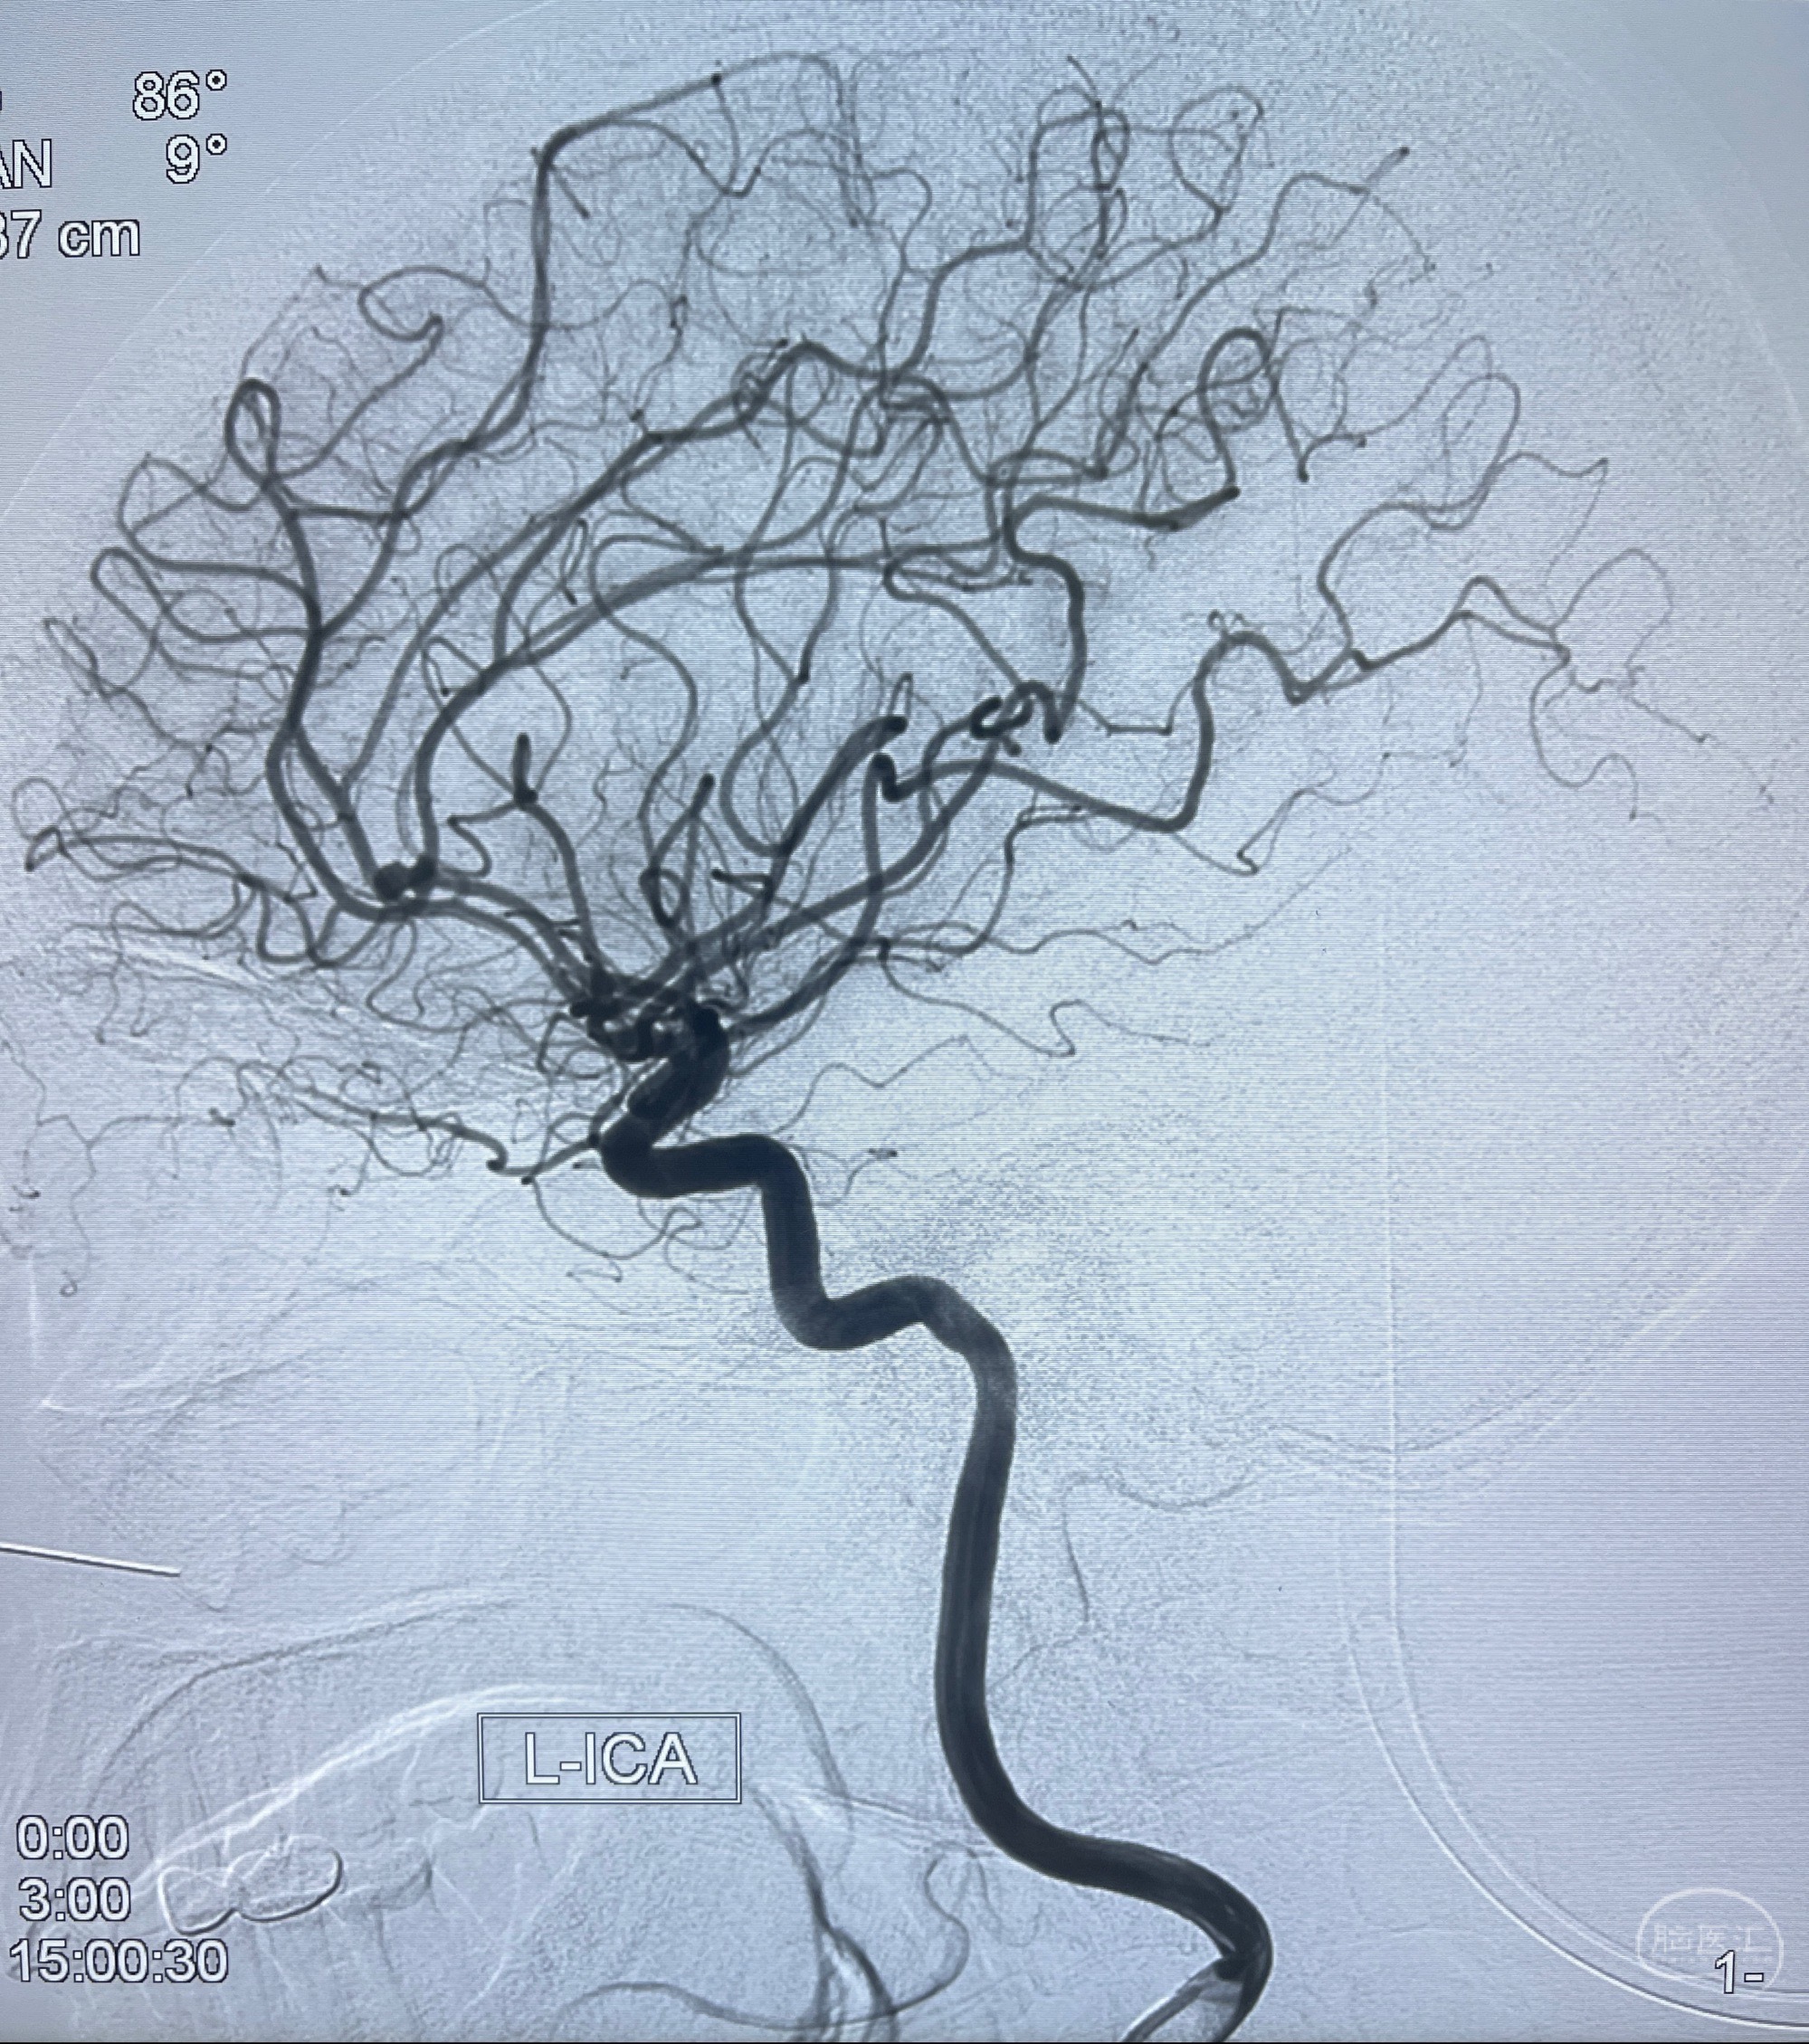

2023-08-23DSA:左侧前交通动脉瘤,左侧A3/4交界处多发动脉瘤